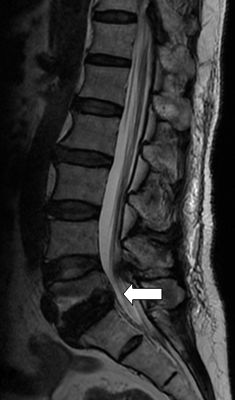

在完善了相关检查后刘阿姨被确诊为腰椎滑脱症—腰5椎体II度向前滑脱。

腰5椎体2度

向前滑脱

脊髓受压变形

术后腰5椎体

完全复位

脊髓压迫

完全解除